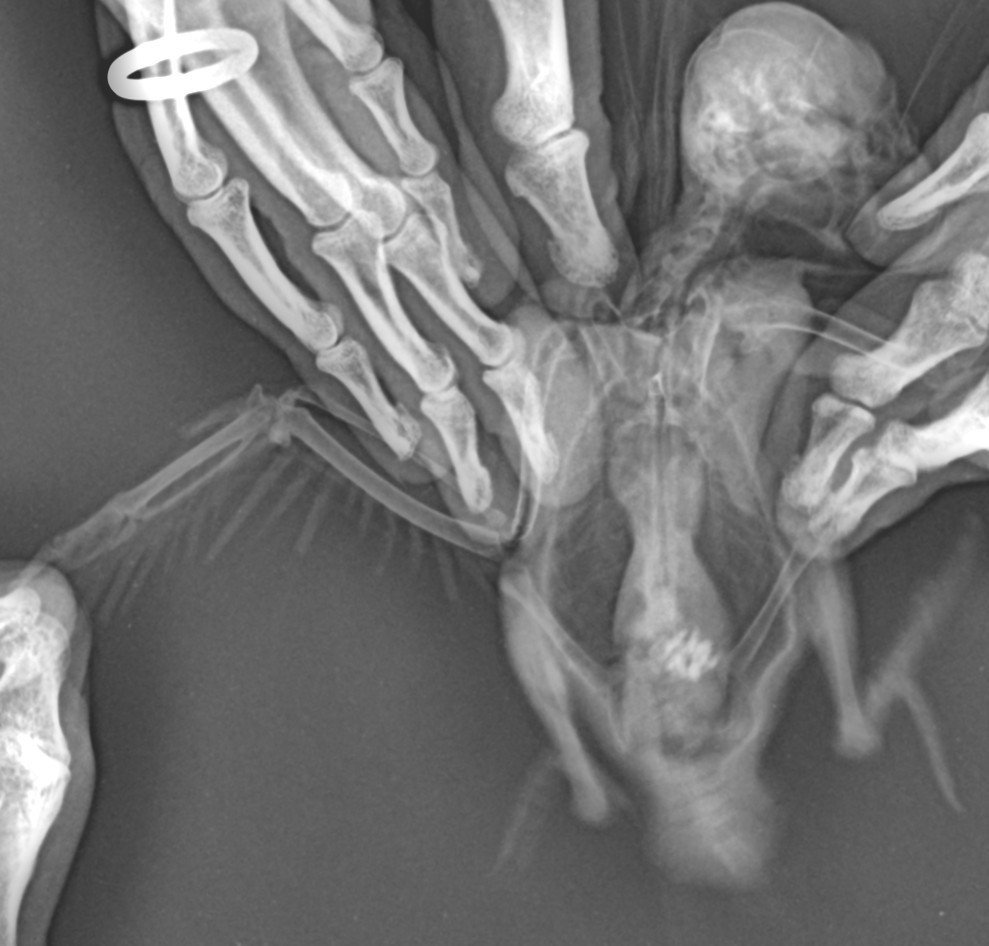

если найдёте рентген то на нём должны быть видны и внутренние органы и суставы ног